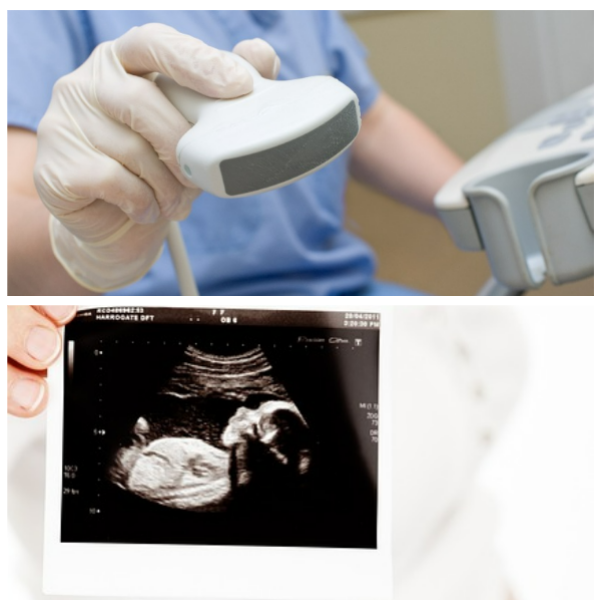

배란초음파를 통해 난소를 보면서 난포가 얼마나 자랐는지 몇 cm인지,

배란이 될 준비를 하고 있는지 등 현재 난소 상황을 선생님과 함께 살펴봅니다.

대개 배란초음파를 통해서 본인이 다낭성난소증후군인지도 살펴볼 수 있습니다.

배란초음파를 보고 나면 배란테스트기에서는 수치만 나와서 정확히 알 수 없었던 부분을 상세하게 볼 수 있으니 마음이 편해지더라고요.